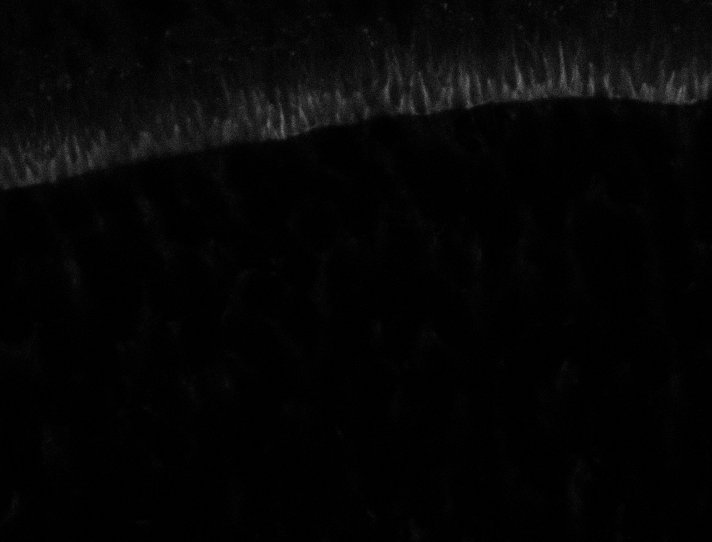

Healthy Retina

Unhealthy Retina